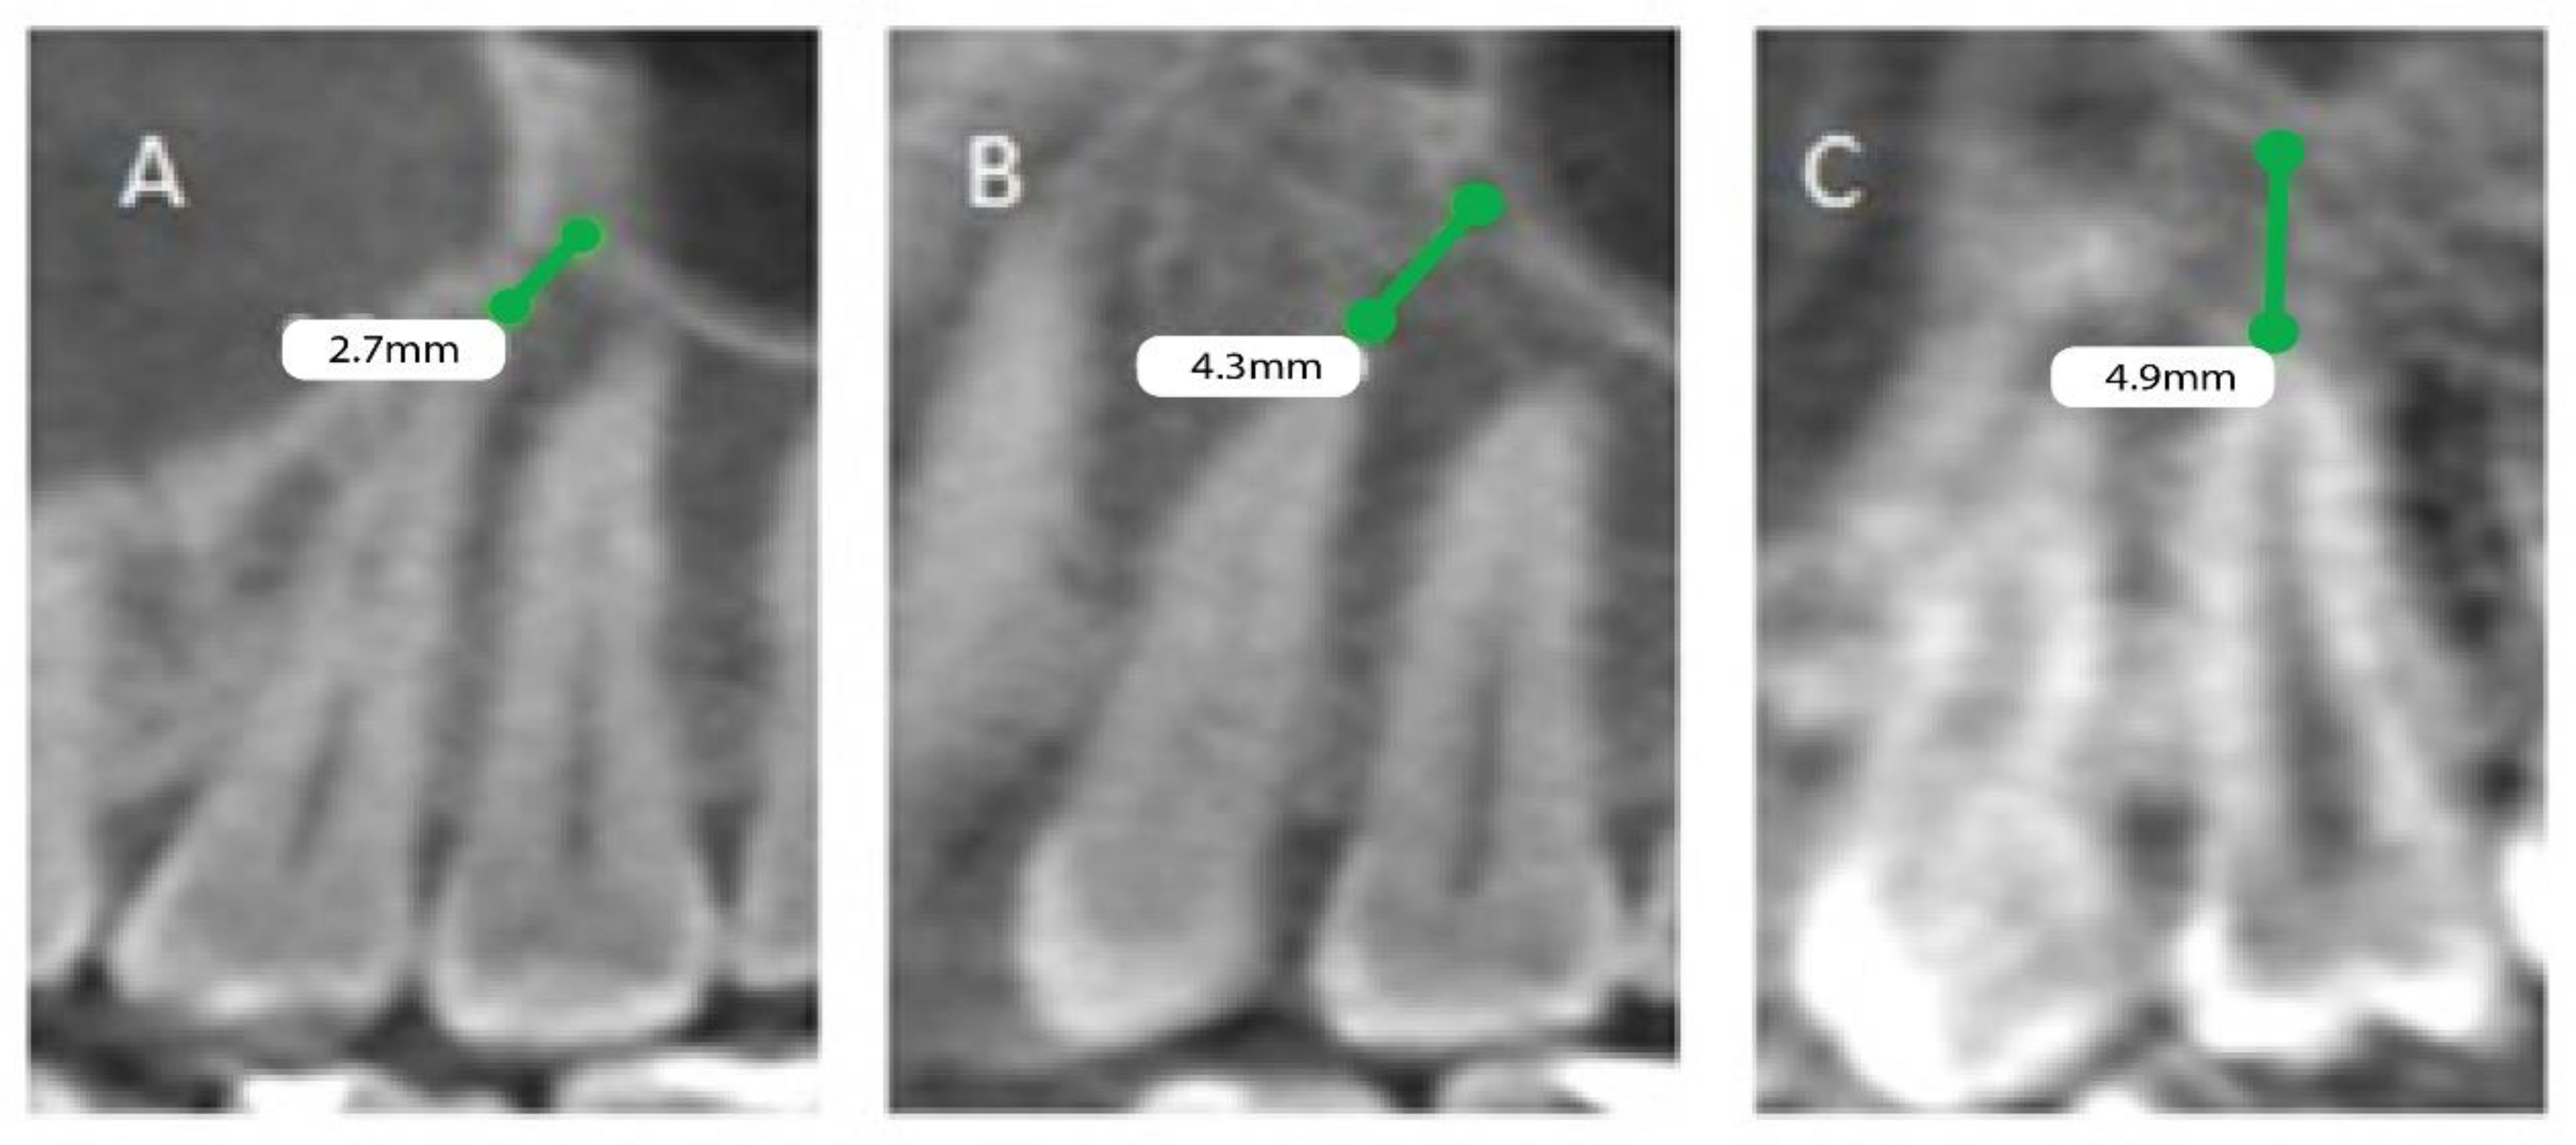

The patients’ files were assessed by the Department of Oral & Maxillofacial Surgery and Diagnostic Sciences, College of Dentistry, Prince Sattam Bin Abdulaziz University, Al-Kharj, Saudi Arabia, to record the gender and the age of the subjects included in the study from September 2020 to December 2020, and further divided as male and female patients, depending on gender and age, into 4 groups (0 to 20, 21 to 40, 41 to 60, and above 60). Mean distances between posterior maxillary roots (PMRs) from different teeth and the maxillary sinus floor (MSF) were measured using a software-calibrated tool. Each measurement was obtained by measuring a line drawn from the MSF to the nearest point of the apex of the root in two views, sagittal and coronal, and the mean distance was calculated (Figure 1, Figure 2 and Figure 3). The distance for each root and each tooth were recorded and transferred to the Excel sheet.

Figure 2.

CBCT sagittal view showing the distance between the maxillary sinus and the root of permanent maxillary (left). (A) First premolar buccal root, (B) first premolar palatal root, (C) second premolar root.